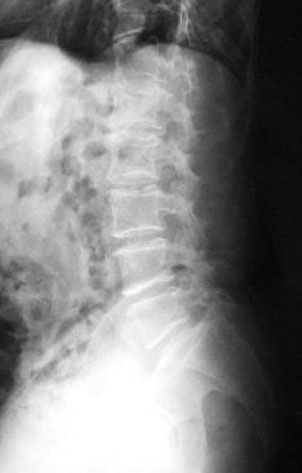

Osteoporosis. Cifosis.

Escoliosis, artrosis, aplastamiento...